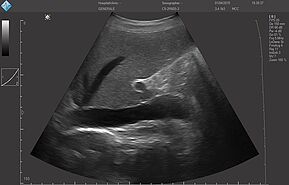

Исследование FAST (Сфокусированная сонографическая оценка при травме) позволяет выявить наличие жидкости в предполагаемых клинических условиях, визуализируя 10 структур или пространств в четырех областях:

- Перикардиальной

- Околопеченочной

- Околоселезеночной

- Тазовой

E-FAST (расширенный-FAST) дополнительно обследует переднюю и боковую плевральную полость (торакальная проекция) для оценки наличия пневмоторакса или плеврального выпота, предположительно гемоторакса у пациентов с травмой.